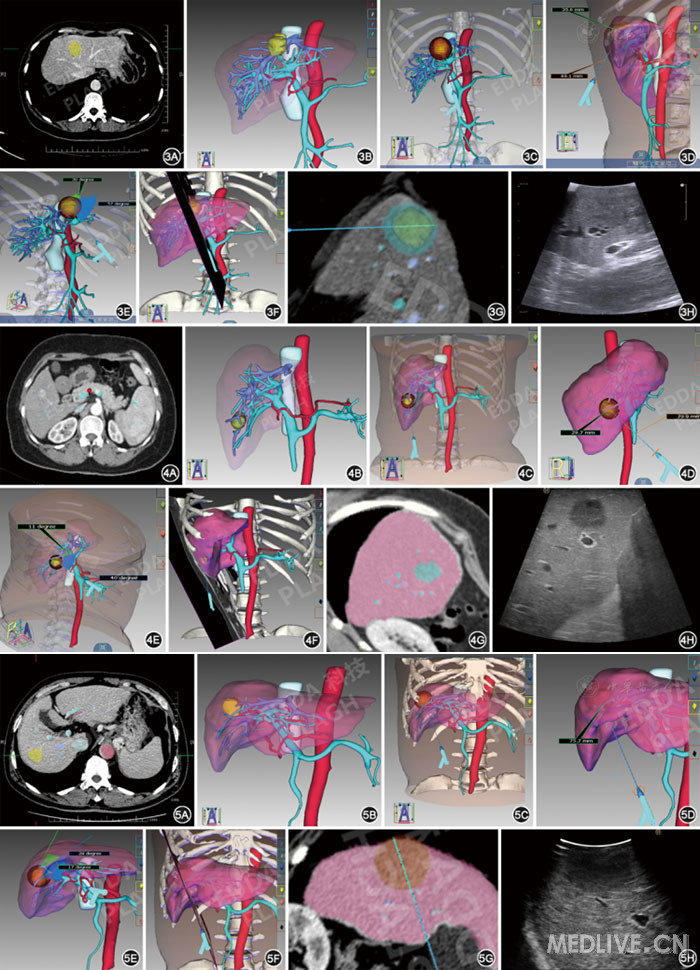

所有肿瘤最大径均<30 mm,分别选用长轴径为30~40 mm的消融针进行规划进针。对位于肝脏左内叶、右前下段、右后上段肿瘤行LRFA术前规划的典型病例图片见图3,图4,图5。

http://webres.medlive.cn/upload/000/307/106

图3-5  IQQA技术平台分别对3例肝脏左内叶肿瘤、肝右前叶下段肿瘤、肝右后叶上段肿瘤行腹腔镜下消融术前手术规划和术中超声检查图像